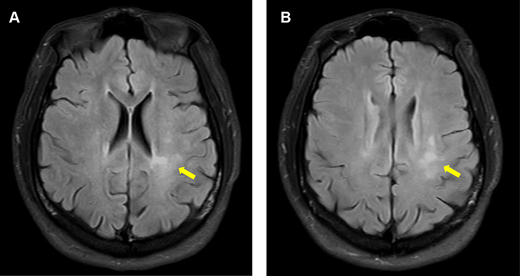

The patient’s magnetic resonance imaging (MRI) of the brain at 5 months after the seizure onset. He had no symptoms. Axial fluid-attenuated inversion recovery (FLAIR) imaging of the brain shows new poorly demarcated hyperintense lesions in the left frontoparietal white matter (arrows).

In May 2024, MRI revealed new subcortical enhancing lesions, despite the absence of symptoms. By November 2024, the patient developed intermittent paresthesia in the left leg and right-sided hyperreflexia. Imaging demonstrated progressive lesions in the brainstem and cervical spine. Neurological examination remained largely normal, apart from hyperreflexia and mild sensory disturbances. Despite extensive testing for infectious and autoimmune etiologies, no alternate causes were identified. Repeated corticosteroid therapy provided symptom relief. The relapsing-remitting radiological course was consistent with an ADEM/MOGAD spectrum diagnosis, and the patient was planned to receive rituximab.